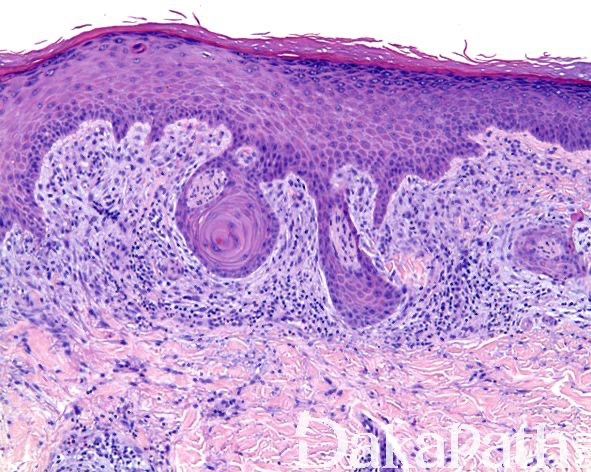

镜下见病变位于真皮浅层,由多个增生的神经束组成,神经束周围可见由鳞状上皮所组成的鞘样结构围绕,神经束内可见轴突、施万细胞和神经束膜细胞;

上皮鞘常与表面上皮相延续,细胞形态温和,可见散在的角化不良的细胞,无核异型性和核分裂象,可能来自于毛囊特别是漏斗部上皮;

表面鳞状上皮常见棘皮瘤样增生;